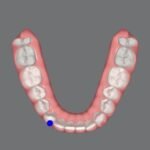

Digital Scanning & Model Analysis

No more messy alginate impressions, comfortable and easy digital scanning using 3shape and meddit intra oral scanners